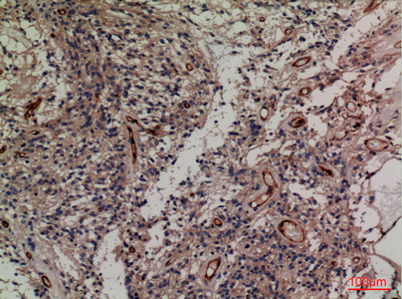

| Dilutions: | Western Blot: 1/500 - 1/2000. IHC-p: 1:100-300 ELISA: 1/20000. Not yet tested in other applications. |